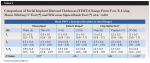

The mean overall changes of facial implant mucosal thickness (FIMT) from T1 to T2, facial implant mucosal level (FIML) from T0 to T3, and midfacial bone sounding (MFBS) from T1 to T3 were 1.2 ± 0.5 (1.6 to 2.9) mm, -0.4 ± 0.4 (-1.6 to 1.0) mm, and 6.0 ± 1.4 (4.0 to 8.5) mm, respectively (Table 2 through Table 4). Comparisons of tissue changes between different parameters (thick vs thin phenotype, V- vs U-shaped facial bone wall defect, and surgery with vs without full-thickness flap reflection) also are presented in Table 2 and Table 3. Regardless of phenotype, defect shape, or surgical technique, the mean FIMT values at T2 were comparable (2.3 mm to 2.4 mm), and all MFBS measurements at T3 were between 3 mm and 4 mm (Table 2 and Table 4). The mean FIML change of -0.4 mm and MFBS change of 6.0 mm translates to a mean vertical facial hard tissue gain of 5.6 mm.

A thin soft-tissue phenotype has been associated with an increased risk of facial implant mucosal dehiscence (ie, recession).19,24,28 Numerous studies have shown the benefits of C-CTG simultaneous with IIPP.17,21,23,29,30 Thickening the FIMT not only can minimize facial mucosal recession, but it may also conceal the underlying implant and/or implant restorative materials. Moreover, thickening the facial mucosa may override the need for underlying facial bone support. A 1-year follow-up study on IIPP and C-CTG on maxillary anterior implants showed an average increase in FIMT of 1.4 mm (0.4 mm to 2.7 mm).29 In the present study, a comparable mean FIMT gain of 1.2 ± 0.5 (0.3 to 2.0) mm with C-CTG grafting was noted after a mean follow-up time of 8.9 (6 to 15) months. Irrespective of initial (T1) soft-tissue phenotype, the average resulting (T2) FIMT of both thick-tissue and thin-tissue phenotype groups was similar (2.3 ± 0.4 mm; Table 2), indicating that thin soft-tissue phenotype is likely to benefit more from this phenotype modification procedure. The changes in FIML and MFBS were comparable between thick and thin phenotype groups (Table 3 and Table 4).